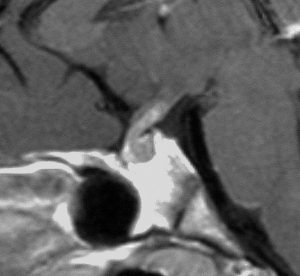

血清HCGが2.1mIU/ml,尿崩症で発症した思春期男児です。石灰化はありませんし,脂肪組織なども混在しません。生検術をしなくてもgerminomaと診断できます。でも簡単なので,経鼻的な生検術を行った方がいいです。

この例は18歳,HCG 0.1mIU/ml,尿崩症で発症しました。神経下垂体ジャーミノーマなので,下垂体前葉のみが残って後葉から視床下部が腫瘍化しています。よくよく見ると松果体にもごく小さな腫瘍があります。右のCISS画像で松果体の腫瘍化が明瞭です。

経鼻生検術で下垂体後葉部分がgerminomaということを確認してからICE (IFO/CDDP/VP-16)を1コース加えて3週間後の画像です。腫瘍は灰白隆起の部分を残してほぼ消失しています。松果体部の腫瘍も消えています。典型的なgerminomaの化学療法反応性を示しています。下垂体前葉機能は正常,尿崩症も少し良くなりました。